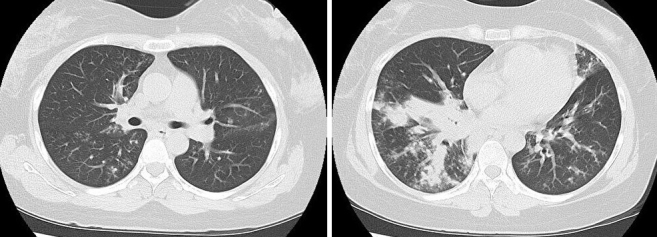

Necrotizing Pneumonia Caused by Community-acquired Methicillin-resistant Staphylococcus aureus Following Influenza.

Abstract Image